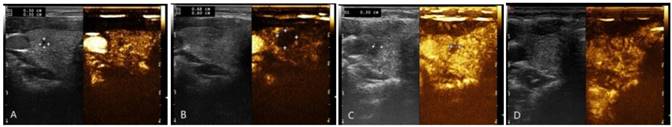

The volume of nodules before ablation, at one month and three months after ablation were1.02 ± 4.24 mL,0.29 ± 0.72mL,and 0.15 ± 0.87mL, respectively. There was statistically significant difference (P<0.05). Figure 3 showed the volume change of nodule after RFA comparing to before ablations.

Figure 3

Changes of the nodule volume before and after RFA treatment, and real-time evaluation was carried out with contrast-enhanced ultrasound. A: before ablation. B: right after ablation. C: one month postoperatively. D. three months postoperatively: ablated lesion was completed absorbed.

The volume reduction ratio (VRR) of thyroid nodulesat one month and three months postoperatively were 64.12%and 85.54%, respectively. There was statistically significant difference (P<0.05) (See Table 1 for details).